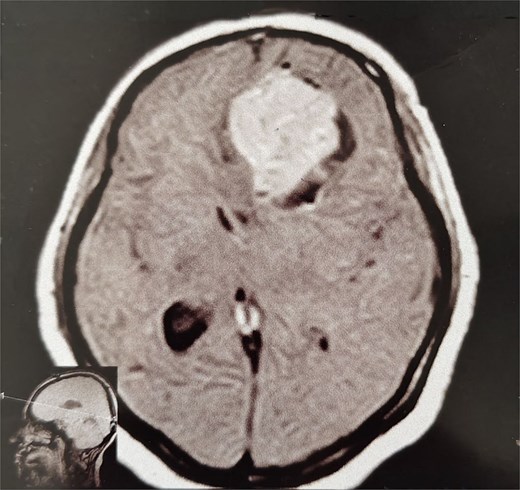

A 44-year-old right-handed woman presented with a two-month history of headache and blurred vision. Her medical history included hypertension and type 1 diabetes mellitus. She reported gradually worsening intermittent headache and bilateral visual blurring, more pronounced in the right eye. Symptoms exacerbated with physical exertion and were unrelieved by analgesics, leading to her referral. Examination revealed a conscious, alert patient with right eye proptosis. Visual acuity was 6/6 (left eye) and 6/9 (right eye). Fundoscopy identified bilateral Grade 3 papilledema. Non-contrast brain CT demonstrated a well-defined, isodense, dural-based extra-axial lesion in the left frontal region with a cystic component, measuring approximately 5.5 × 4.3 × 4.2 cm. It was associated with mild perilesional edema, mass effect, and a subtle contralateral falx shift. The initial impression was an atypical meningioma (Fig. 1). Subsequent MRI confirmed a large, falcine-based lesion that appeared isointense on T1- (Fig. 2) and T2-weighted images, demonstrating intense homogeneous enhancement post-contrast (Fig. 3). Signal voids suggested calcifications. The patient underwent gross total excision via a bilateral frontal craniotomy. The tumor was intradural and extra-axial, elevating the frontal lobe and was easily accessible; therefore, neither neuronavigation nor other intra-operative localization aids were utilized. Intraoperatively, the olfactory tract could not be clearly identified. A gap in the anterior cranial base was noted, but as there was no evidence of dural invasion or cerebrospinal fluid leak, no sealant was required. Gross examination of the resected specimen revealed a well-circumscribed, white nodule. Microscopically, sections showed benign spindle cell proliferation with alternating Antoni A and Antoni B areas (Fig. 4). Antoni A regions displayed nuclear palisading and Verocay bodies (Fig. 5), while Antoni B areas were edematous and myxoid (Fig. 6). No mitotic figures or atypia were seen. The definitive diagnosis was a benign olfactory groove schwannoma, notable given the initial radiological suspicion of meningioma. Her postoperative course was uneventful. A postoperative non-contrast CT brain obtained 48 hours after surgery confirmed gross total resection (Fig. 7). She was discharged with scheduled follow-up to monitor recovery and visual symptoms.

MRI brain without IV contrast (T1 sequence) showing a well-circumscribed hypointense mass with areas of heterogeneity occupying the right frontal lobe, closely related to the midline structures and falx cerebri.

MRI brain with IV contrast (sagittal midline view) showing a homogeneously enhancing mass based on the cribriform plate of the ethmoid, displacing the frontal lobe upward and posteriorly.